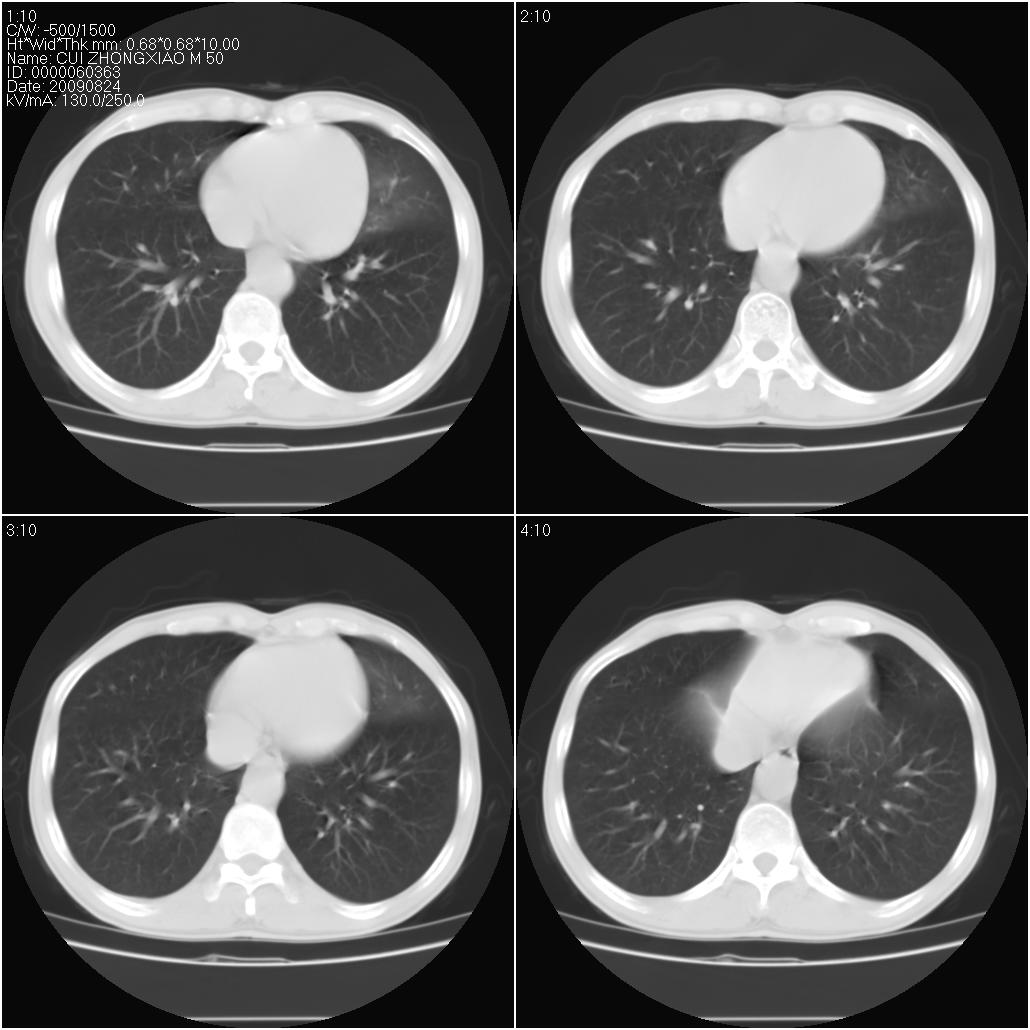

标题: CT21851:男性,50岁。间断性咳嗽半年。 [打印本页]

标题: CT21851:男性,50岁。间断性咳嗽半年。

磨玻璃样改变(左肺及右肺上叶前段),边缘模糊,考虑炎症,建议严格抗炎治疗后复查除外肺泡蛋白沉积症或肺泡出血(病人有咯血吗) 肺泡癌.

双肺磨玻璃征改变。。。支持楼上